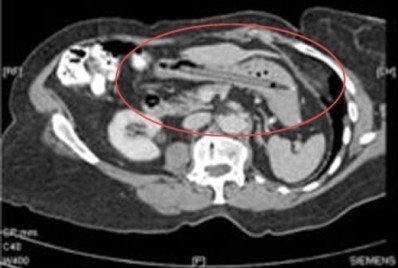

Mô tả trường hợp này trên Tạp chí Y khoa Anh, bác sĩ chuyên khoa tiêu hóa, Oliver Waters tại bệnh viện hoàng gia Devon & Exeter (Anh), cho biết bệnh nhân đến gặp ông khi bị giảm cân và mắc tiêu chảy. Ông từng chẩn đoán bà mắc viêm túi thừa nghiêm trọng. Sau đó, quá trình chụp CT phát hiện "một vật thể ngoại lai dài trong dạ dày".

Người phụ nữ này nhớ lại đã vô tình nuốt phải cây bút nhiều năm trước, nhưng kỹ thuật X-quang thời ấy không tìm thấy dấu vết của cây bút.

Theo Daily Mail, chiếc bút không hề phá hủy dạ dày của bệnh nhân. Thực tế, các triệu chứng khiến bà đến gặp bác sĩ cũng đã "bỗng dưng" mà hết. Tuy nhiên, bác sĩ vẫn quyết định lấy cây bút ra để nó không đâm thủng thành dạ dày của bà trong tương lai.

Sau khi 'tắm' trong axit dạ dày suốt hai thập kỷ rưỡi, cây bút đã bị ăn mòn và vỏ nhựa bong tróc. Nhưng, đáng ngạc nhiên là, mực trong bút vẫn có thể sử dụng và bút vẫn viết được!